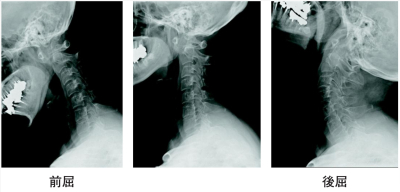

握力は右 16 kg、左 14 kg。両手にボタンホール変形を認める。左示指と中指とに軽度の感覚鈍麻を認める。下肢の筋力は徒手筋力テストで5である。腱反射に異常を認めない。歩行障害を認めない。入院治療については、次男の受験を控えていることから家族内で相談したいとの希望があったため、頸椎カラーを処方した。頸椎エックス線写真を別に示す。